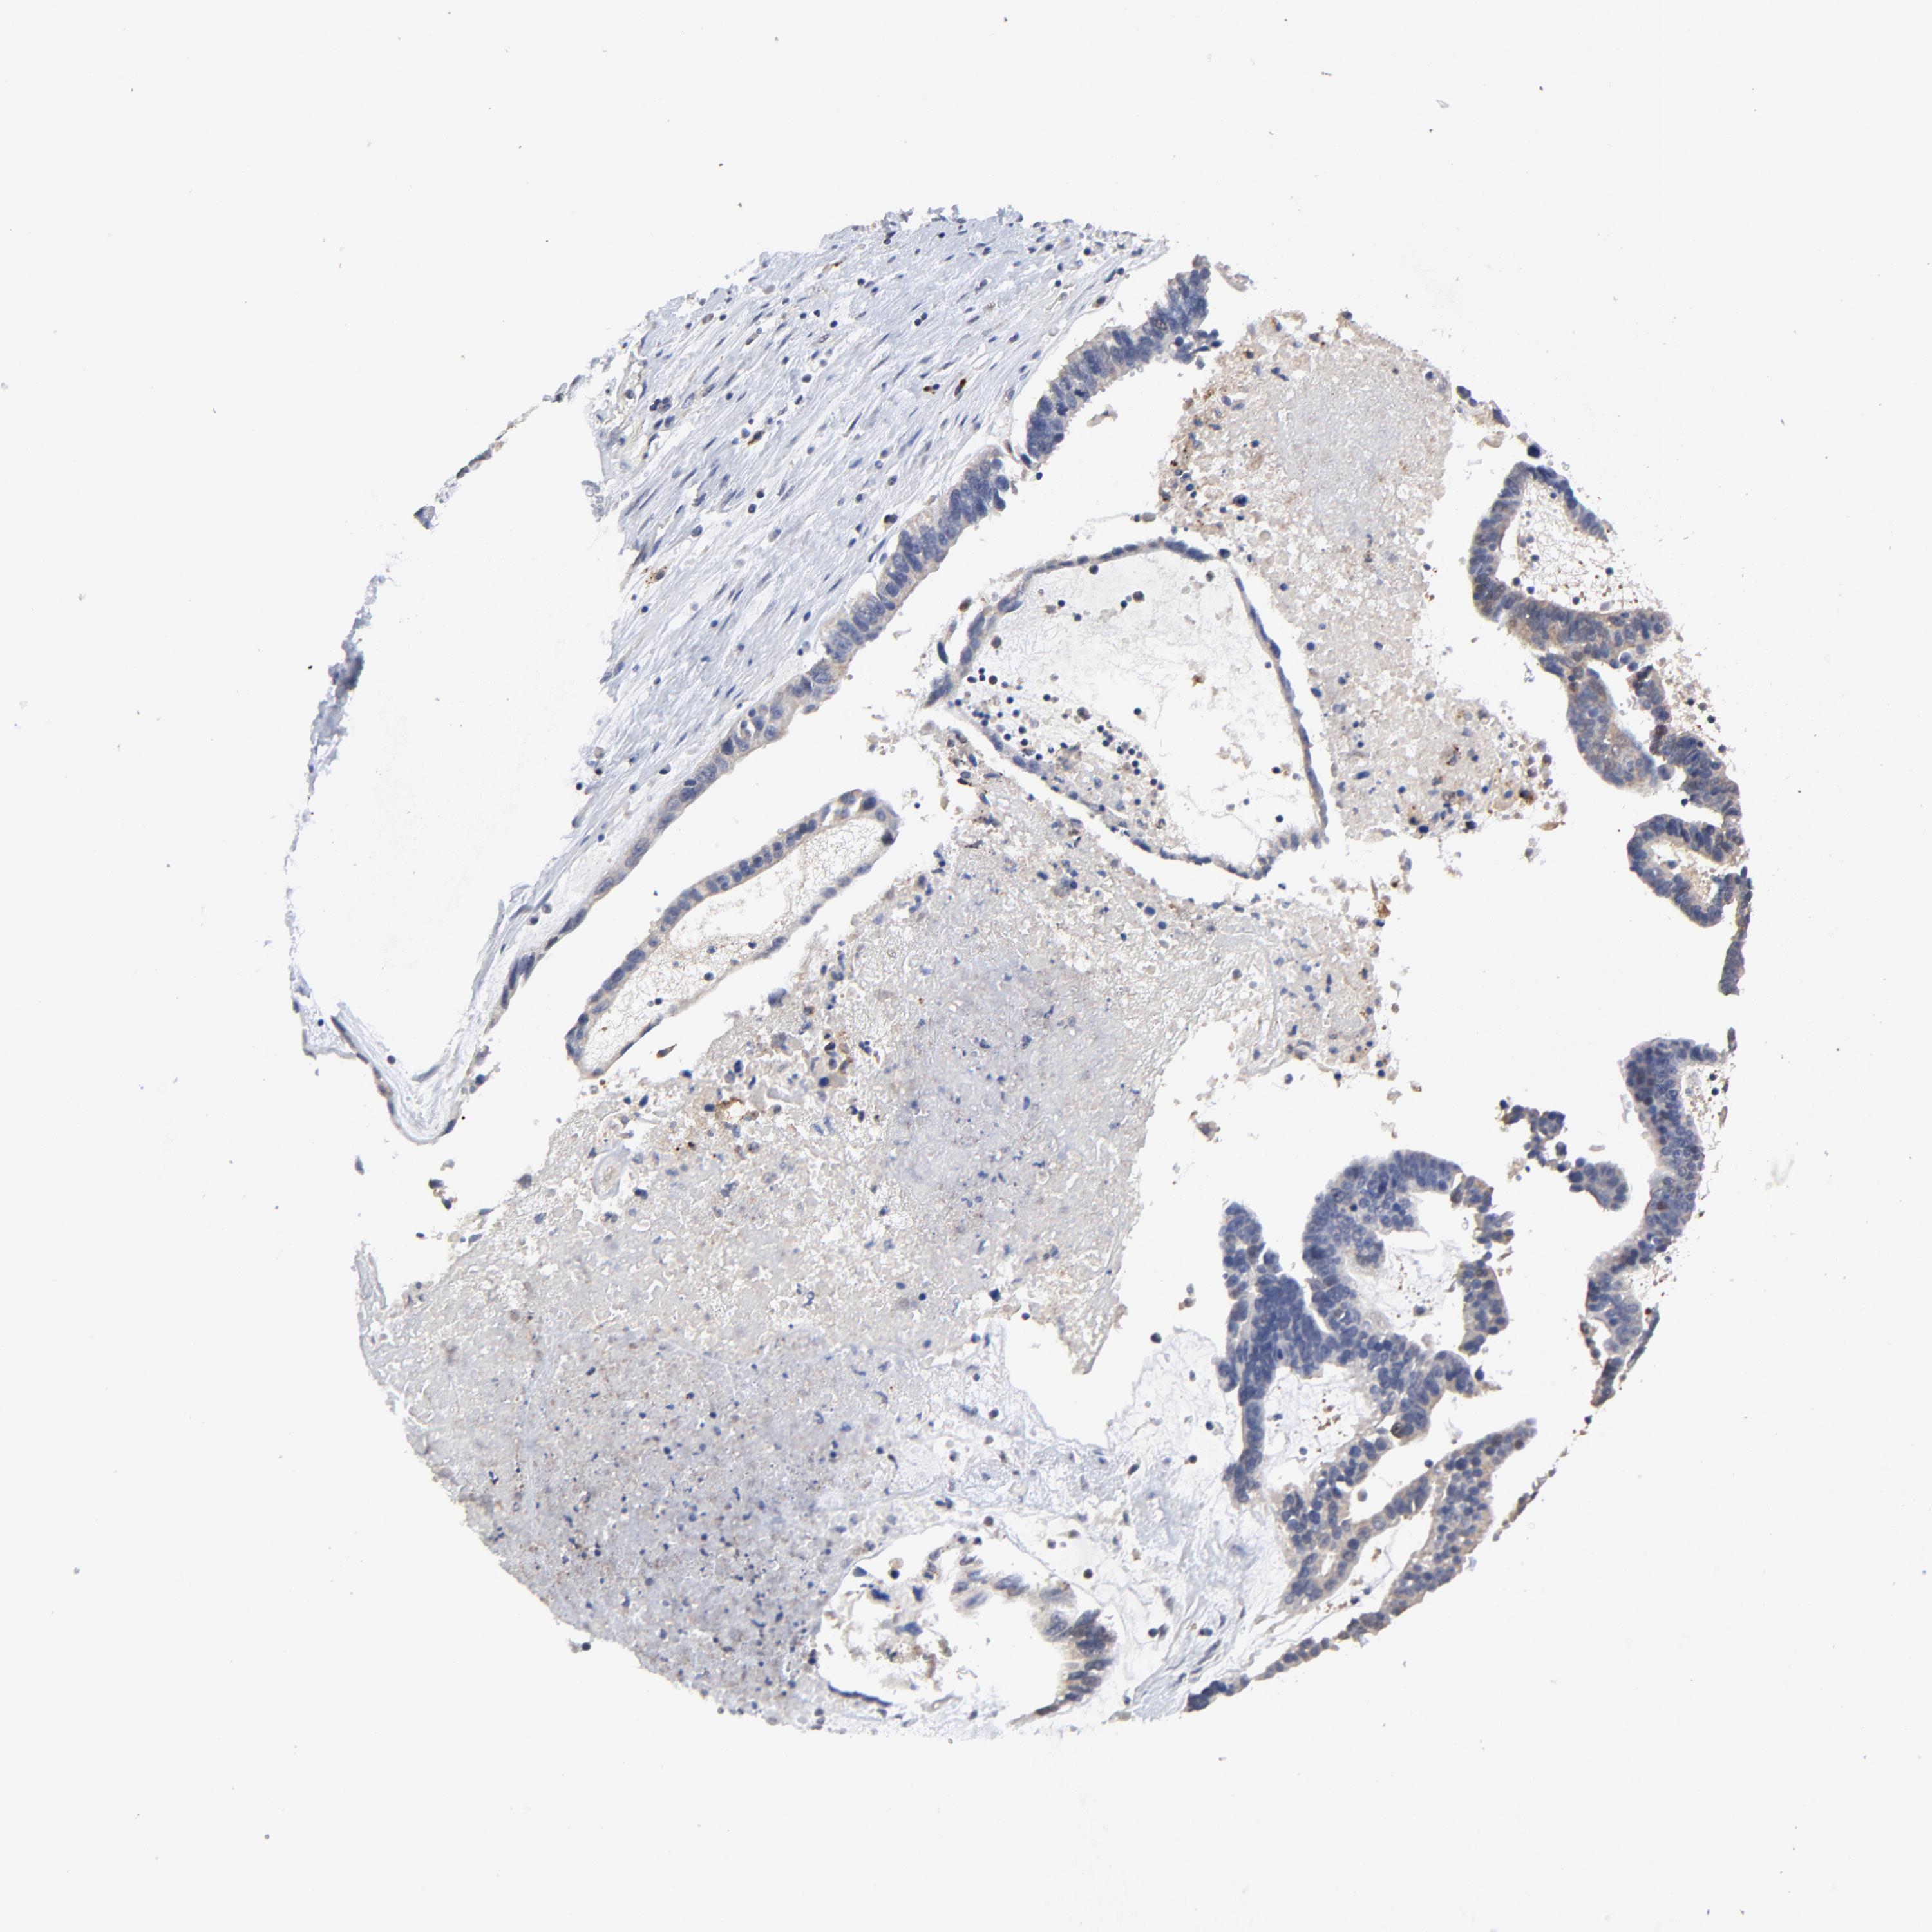

OVARIAN CANCER - Protein expressioni

A mouse-over function shows sample information and annotation data. Click on an image to view it in a full screen mode. Samples can be filtered based on level of antibody staining by selecting one or several of the following categories: high, medium, low and not detected. The assay and annotation is described here.

Note that samples used for immunohistochemistry by the Human Protein Atlas do not correspond to samples in the TCGA dataset.

Antibody stainingi

Antibody staining in the annotated cell types in the current human tissue is reported as not detected, low, medium, or high, based on conventional immunohistochemistry profiling in selected tissues. This score is based on the combination of the staining intensity and fraction of stained cells.

Each image is clickable and will lead to virtual microscopy that enables deeper exploration of all samples and also displays staining intensity scores, fraction scores and subcellular localization as well as patient and tissue information for each sample.

Antibody HPA003162

Antibody CAB005191

Staining

High

Medium

Low

Not detected

Intensity

Strong

Moderate

Weak

Negative

Quantity

>75%

75%-25%

<25%

None

Location

Nuclear

Cytoplasmic/membranous

Cytoplasmic/membranous,nuclear

Cystadenocarcinoma, mucinous, NOS

Carcinoma, endometroid

Cystadenocarcinoma, serous, NOS

Carcinoma, NOS